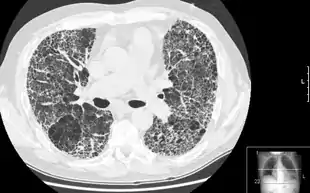

|  HRCT of lung showing extensive fibrosis possibly from usual interstitial pneumonitis. There is also a large emphysematous bulla. | |

HRCT is used for diagnosis and assessment of interstitial lung disease, such as pulmonary fibrosis, and other generalized lung diseases such as emphysema and bronchiectasis.

HRCT may be diagnostic for conditions such as emphysema or bronchiectasis. While HRCT may be able to identify pulmonary fibrosis, it may not always be able to further categorize the fibrosis to a specific pathological type (e.g., non-specific interstitial pneumonitis or desquamative interstitial pneumonitis). The major exception is UIP, which has very characteristic features, and may be confidently diagnosed on HRCT alone.[9]